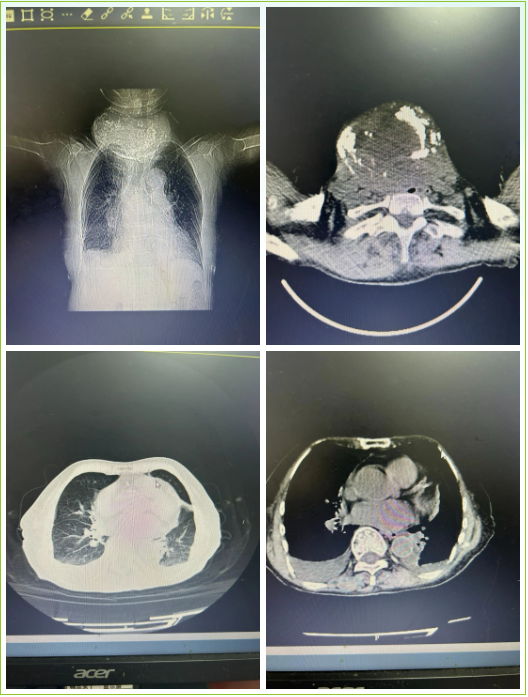

CT检查提示患者的甲状腺明显肿大,气管、食管压迫明显,气管直径约7MM,颈动脉、颈静脉因肿块挤压移位,并和肿块粘连,界限不清。经甲状腺外科会诊后:患者颈部巨大肿块,考虑结节性甲状腺肿,肿瘤巨大,压迫气管明显,手术指针明确。如果目前不采取手术治疗,肿瘤继续生长进一步对气管持续进行挤压,宛如一颗定时炸弹,随着时间推移,患者气管必将出现更加狭窄甚至梗阻及窒息死亡可能,急需解除气管压迫,否则会引起窒息,导致患者死亡。但是患者年龄大,身体条件差,手术风险巨大。